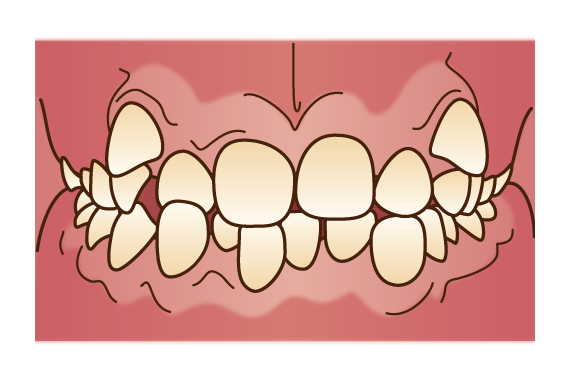

受け口

受け口とは、上顎よりも下顎が前に突出している状態です。歯や歯茎、顎関節に負担がかかり、咀嚼機能が低下します。また、よく噛めないことで胃腸にも負担がかかり、胃痛や胃酸過多などのトラブルに繋がるケースも少なくありません。受け口は、3~4歳頃の比較的早い時期から治療を始めた方がよいとされています。受け口の中でも骨格に大きな問題があるケースは、外科的な手術が必要になる場合があります。

受け口とは、上顎よりも下顎が前に突出している状態です。歯や歯茎、顎関節に負担がかかり、咀嚼機能が低下します。また、よく噛めないことで胃腸にも負担がかかり、胃痛や胃酸過多などのトラブルに繋がるケースも少なくありません。受け口は、3~4歳頃の比較的早い時期から治療を始めた方がよいとされています。受け口の中でも骨格に大きな問題があるケースは、外科的な手術が必要になる場合があります。